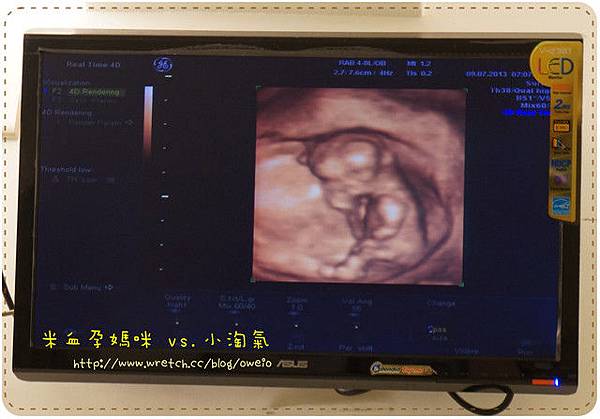

最後附上一張小淘氣12W的4D圖

不過說實在的...怎麼有點嚇人

東凸一塊西凸一塊

很多人都說胎兒在媽媽肚子裡時很像外星人

果然...(千萬不可以讓小淘氣知道!對胎教不好!喔齁齁~)

不過目前看到短短肥肥的手臂,還是很想噗哧~